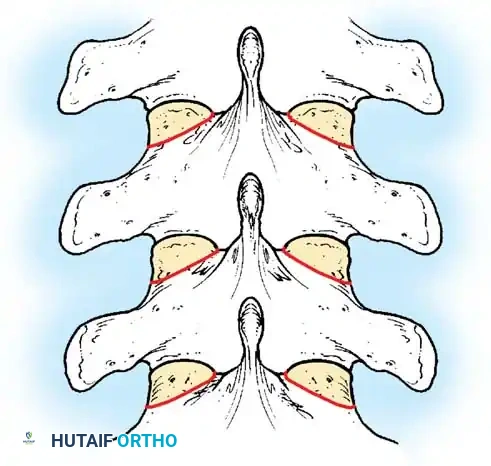

Biomechanics of Bone Grafting

Bone graft incorporates most effectively under compressive loads and is biologically disadvantaged in environments of distraction. Therefore, in scoliosis correction, if autogenous bone is limited, it should be preferentially concentrated on the concave side of the curve, which is subjected to compressive forces, rather than the convex side, which experiences tension. Furthermore, the farther the fusion mass is placed from the instantaneous axis of rotation, the more effectively it will neutralize movement across that axis.